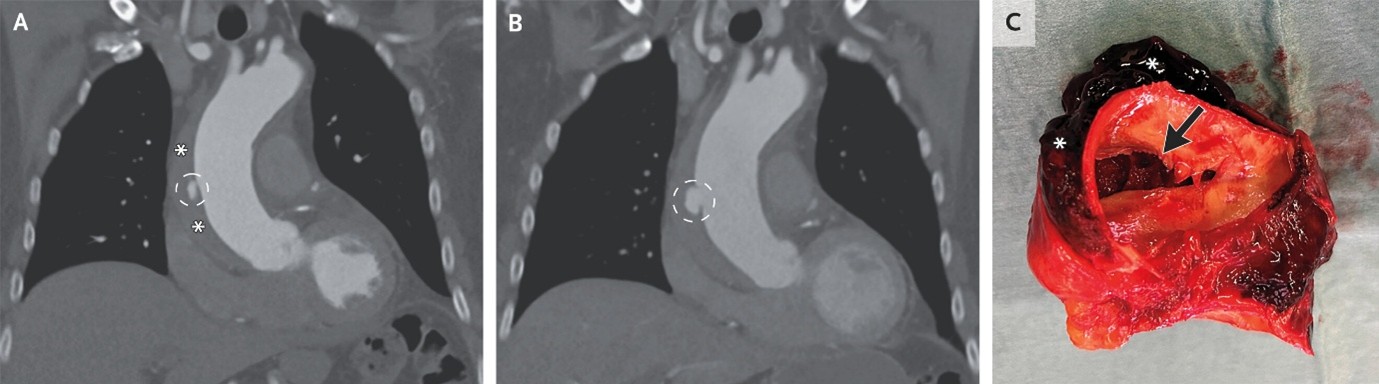

(9). Aortic Intramural Hematoma

Sjoerd Bouwmeester et al, published December 6, 2025 ,DOI: 10.1056/NEJMicm2506150

Abstract

An 80-year-old man presented to the emergency department with a 12-hour history of pleuritic chest pain and an elevated d-dimer level. A CT scan showed an ulcerlike projection in the ascending thoracic aorta.